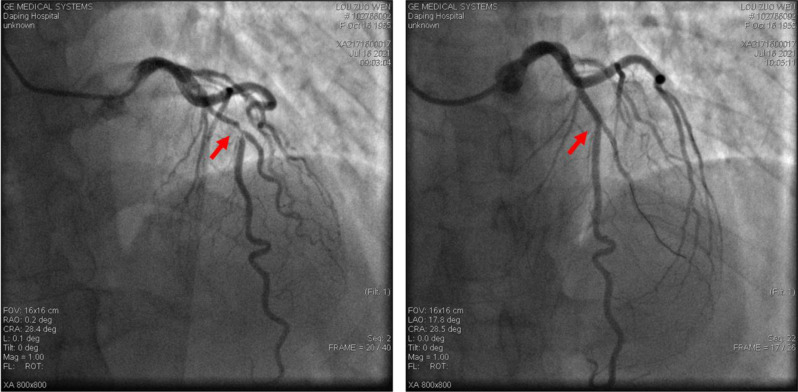

Methods: From October 2020 to June 2023, 14 patients, with unstable angina and resectable lung cancer received PLHS. All procedures were performed in a hybrid operating room. Drug-eluting stents (DES) were implanted during PCI. Lobectomy was carried out within one hour after PCI.

Results: Procedural success was 100%. All the patients subjected to PLHS were alive after 12 months of follow-up; 2 patients (14.29%) died due to distant metastasis within 12-24 months post-PLHS. There were no intraoperative complications, or 30-day- and 3-month-mortality. Except for one patient who suffered pneumothorax, no other postoperative complications, including severe bleeding, or in-stent restenosis, occurred in the 31.7 ± 10.9 months follow-up.